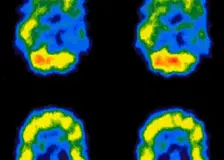

Šedá hmota mozková: její funkce a zajímavosti o ní

Šedá hmota mozková je tvořena především těly nervových buněk a slouží ke zpracování informací v mozku. Podílí se na myšlení, paměti, učení, emocích, řeči, rozhodování i řízení pohybů. Nachází se v mozkové kůře i hlubších strukturách mozku a spolupracuje s bílou hmotou, která zajišťuje přenos nervových signálů. Její zdraví podporuje pravidelný pohyb, kvalitní spánek, mentální Continue Reading The …